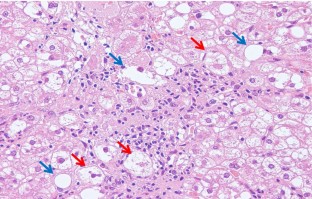

Nonalcoholic fatty liver disease (NAFLD) is based on the concept of pathological morphology as well as clinical findings, and is broadly categorized into nonalcoholic fatty liver (NAFL) and nonalcoholic steatohepatitis (NASH). The differential diagnosis between NAFL and NASH is important because NASH has the potential to progress to cirrhosis and hepatocellular carcinoma. NAFL is simple hepatic steatosis without hepatocellular injury, while NASH is characterized by macrovesicular steatosis, inflammation, and ballooning hepatocytes with a predominantly centrilobular (zone 3) distribution. Liver biopsy is a useful test for diagnosing NAFLD, but it is invasive. Therefore, various noninvasive methods including diagnostic imaging have been developed in recent years. To verify their usefulness, it is necessary to clarify in detail how the pathological findings are reflected in the image findings as imaging and histopathological findings are closely related. We describe the main histological features of NAFLD, i.e., steatosis, inflammation, ballooning hepatocytes, Mallory-Denk bodies, and fibrosis, as well as the evolutional process to liver cirrhosis.

Fig. 3